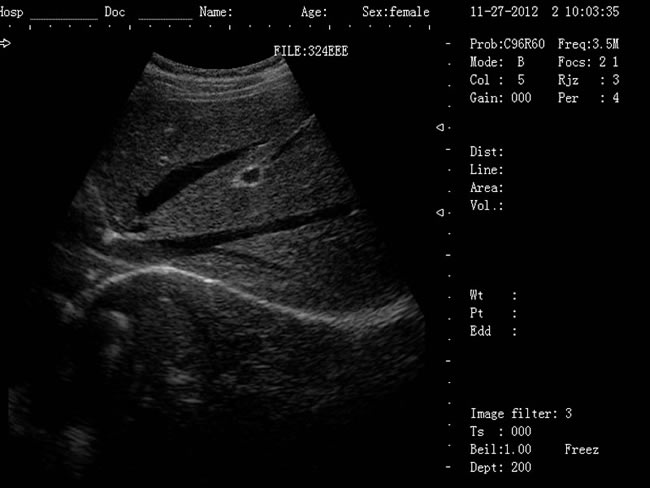

徐州大為DW-500筆記本b超機 1、DW-500產品特點: (1)DW-500是一款高陣元、高清晰度、多功能的筆記本式超聲診斷儀。 (2)它的小巧輕便,圖像清晰,操作方便、續航能力強,在城市、鄉鎮、戶外等,各種環境下會診的超強優越性。 (3)多種充電方式更保證了在不同環境下檢查會診。 2、DW-500新增3大看點: (1)5-7小時超長待機時間 (2)12.1英寸LED液晶顯示器 (3)全數字96陣元 3、一流的數字成像技術,圖像更清晰 (1)DBF全數字波束形成 (2)DRF實時逐點動態接受聚焦 (3)DRA實時動態聲速變跡 (4)THI組織諧波成像 (5)RDA實時動態孔徑成像 (6)DFS數控動態頻率掃描 (7)RDF實時動態濾波 4、靈活方便的操作系統 (1)12.1英寸LED液晶顯示器 (2)背光硅膠鍵盤,更舒適耐磨,暗室中使用不再煩惱 (3)智能化菜單,人機對話輕松快捷 (4)顯示穿刺引導線,角度和位置可調 (5)多倍率顯示,病變診斷更準確 (6)外接USB存儲,圖像上傳更方便 (7)大容量的電影回放,圖像自動循環演示 (8)豐富的測量功能:距離,周長,面積,體積,產科測量表,心臟軟件包等 (9)顯示模式:B、B+B、4B、B+M、M (10)電影回放:≥256幀,可連續回放或逐幅查看 (11)具有穿刺引導功能,穿刺線位置可調節 (12)具有碎石定位,動態靶區跟蹤功能 (13)主機尺寸:330x289x70mm(長x寬x高);